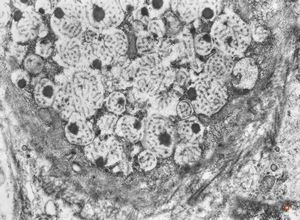

F,31y. | ovary - mucinous carcinoma